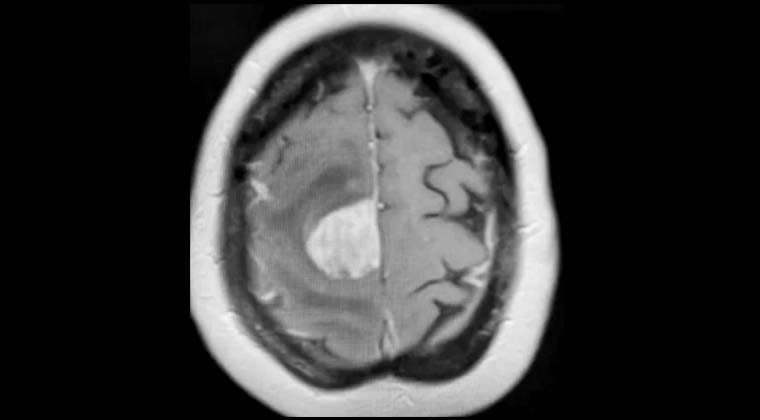

③ Случай 3:

Пациент: мужчина, 65 лет

Кавернозная гемангиома кавернозного синуса

Рисунок 1: 10.06.2020 Планирование лечения Гамма-ножом

Рисунок 2: 06.01.2021, через 6 месяцев после лечения Гамма-ножом очаг значительно уменьшился